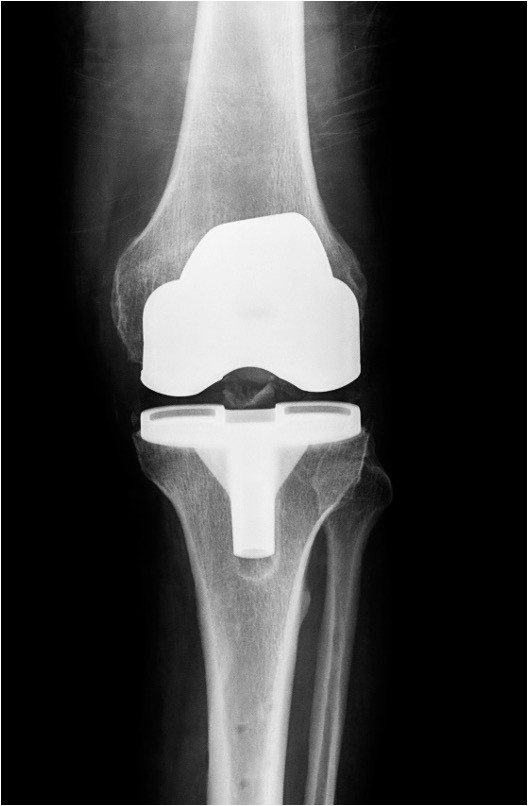

Η αρθροπλαστική γόνατος είναι μία χειρουργική επέμβαση με την οποία ένα προσβεβλημένο γόνατο από οστεοαρθρίτιδα ή άλλες εκφυλιστικές βλάβες αντικαθίσταται από μία ειδικά σχεδιασμένη πρόθεση.

Μία απλή ακτινογραφία επιβεβαιώνει την διάγνωση και την έκταση της βλάβης.

Η επιλογή της πρόθεσης, της χειρουργικής τεχνικής εξαρτάται από την ηλικία, το σωματικό βάρος, τις δραστηριότητες και την γενική κατάσταση της υγείας του ασθενή.

Ο τύπος της αρθροπλαστικής που θα χρησιμοποιηθεί επιλέγεται αφού έχουν εκτιμηθούν προεγχειρητικά και συζητηθούν με τον ασθενή διάφοροι παράμετροι.